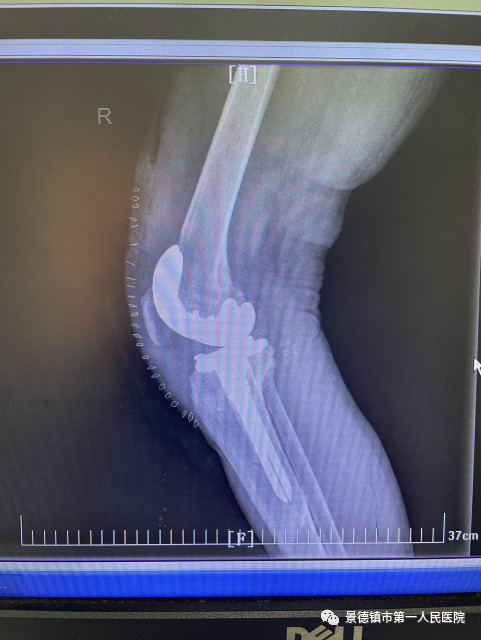

20多年前,年轻的程小华打工时意外坠楼,却因家中贫困没有及时治疗,导致了腿部严重畸形。这么多年,程小华右腿因为没有得到治疗,旧伤愈演愈烈,关节向外侧翻,走路一瘸一拐,膝盖处由于骨头错位传来阵阵疼痛,让他痛苦不堪。如今,生活条件明显改善了,母亲和姐姐对于他常怀着愧疚的心情,在他亲友的鼓励下,在对健康身躯的热切渴望下,程小华终于走上了求医路,迫切地希望自己的腿能够好起来,能够陪伴自己的孩子。

经过多次术前讨论,袁志峰与手术团队医师刘会文共同讨论出手术方案。行表面膝关节置换术,尽量的保留患者更多的骨量,为20年甚至30年以后面临的再次置换提供一个充足的骨量储备。并利用目前医疗领域新的3D数字打印技术,精准进行截骨和假体安放,有效避免术后患者双侧因软组织不平衡而造成的力线偏移,假体就更加稳定,使用的寿命更加长。

8月23日,是程小华“重获新生”的日子,1个半小时的手术过程,在程小华家人心中像过了一个世纪那么长。当得知手术非常成功后,他的家人心中如同放下一块大石。这段时期,骨二科的医护人员经常在程小华的病房指导他复健,9月17日出院时,程小华已经可以像正常人一般行走,他仍然需要积极进行康复锻炼,逐步恢复腿部肌肉。